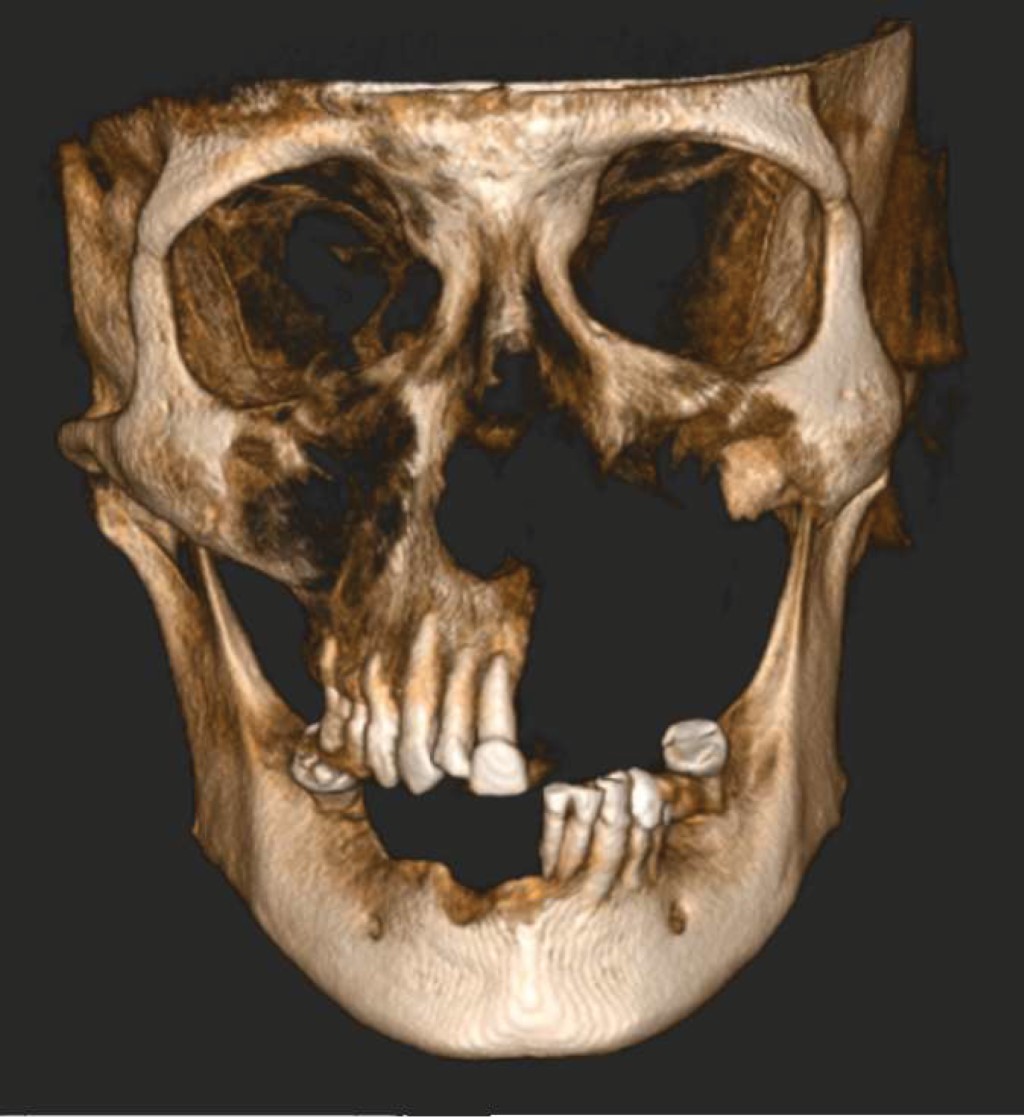

After a month and a half of presenting COVID-19 infection, he presented an increase in volume, an erythematous area, painful on palpation and the presence of abscesses in the fundus region of the left maxillary vestibule, for which he went to a dentist and drained the aforementioned abscesses. Indicates to perform orthopantomography (Figure 1) and start treatment with clindamycin and amoxicillin/clavulanic acid. He also goes to the otolaryngologist who indicates a diagnosis of sinusitis and trigeminal neuralgia for which he indicates pregabalin, B complex and carbamazepine.

Figure 1